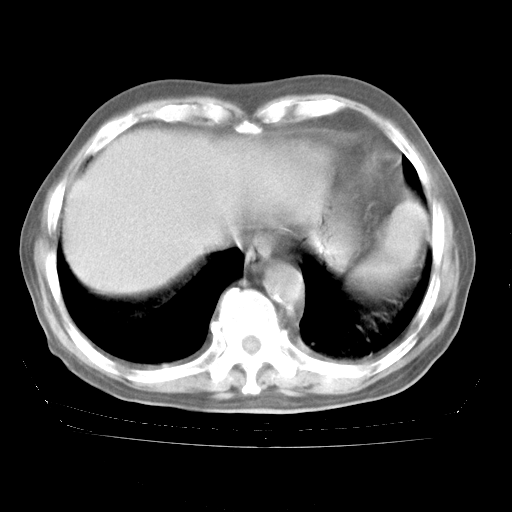

今天部分检查

轻微咳嗽,无痰,(体温正常时)R20次/分,P75次/分,双肺底、腋下可闻及少量捻发音。下肢轻度浮肿。

血常规:白细胞9.11×109/L,N0.92,L5.64,血小板39.2×109/L,HB148g/L,ESR2mm/H。

尿常规:潜血+

血生化:总蛋白69.71g/L,白蛋白38.40g/L,球蛋白31.31g/L,CRP27.9mg/L,尿素氮11.98mmol/L,肌酐106μmol/L,乳酸脱氢酶1099 U/L,肌酸激酶108U/L,CK-MB 61U/L。

腹部B超:胆囊壁增厚,肝、胆、胰、脾、肾无异常,肠系膜淋巴结、腹膜后淋巴结无增大。

ECG:右心室增大

心脏超声检查:无右心室增大。

增加治疗:异烟肼、利福平、乙胺丁醇,静滴左氧氟沙星、参麦注射液。甲强龙从80mg暂减为40mg。

强的松3月1日改为10mg qd,4月1日改为10mg qod。3月份以前的减量过程和环磷酰胺疗程需等明天查看记录(我岳父自己做的记录在他家里)。